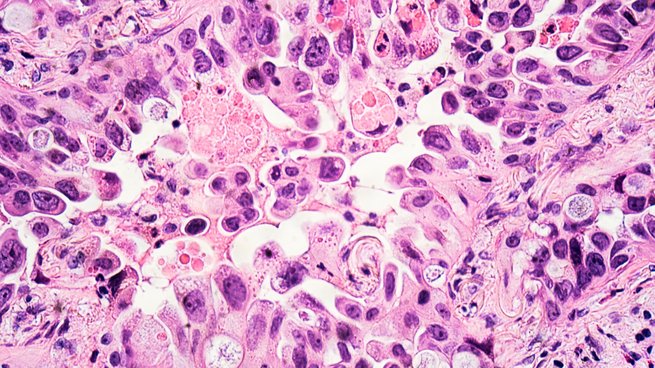

Biobanken lagern weder Geld noch Gold, sondern Blut, Gewebe oder Körperflüssigkeiten von Menschen. Sie sind innovative Speicher für Proben und Daten, ohne die moderne Forschung nicht möglich wäre. Bei bestimmten Krankheiten helfen Biobanken dabei, diese besser zu behandeln. Einige Lungenkrebsarten gehören dazu. Die Bildgeschichte zeigt ein Beispiel, wie die Präzisionsmedizin beim nicht-kleinzelligen Lungenkarzinom zum Einsatz kommt.